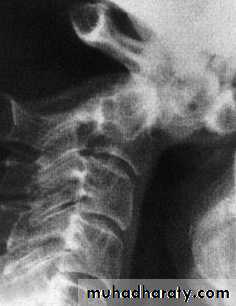

Fracture of C2 ‘Hangman’s fracture’ – fracture of

the pars interarticularis of C2.C2 Odontoid process fracture

C2 pars interarticularis fractures

‘hangman’s fracture’ there are• bilateral fractures of the pars interarticularis of C2 and

• the C2/3 disc is torn;

2. the mechanism is extension with distraction.

This is one cause of death in motor vehicle accidents when the forehead strikes the dashboard.

Neurological damage, is unusual

because the fracture of the posterior arch tends to

decompress the spinal cord.

Nevertheless the fracture

is potentially unstable.